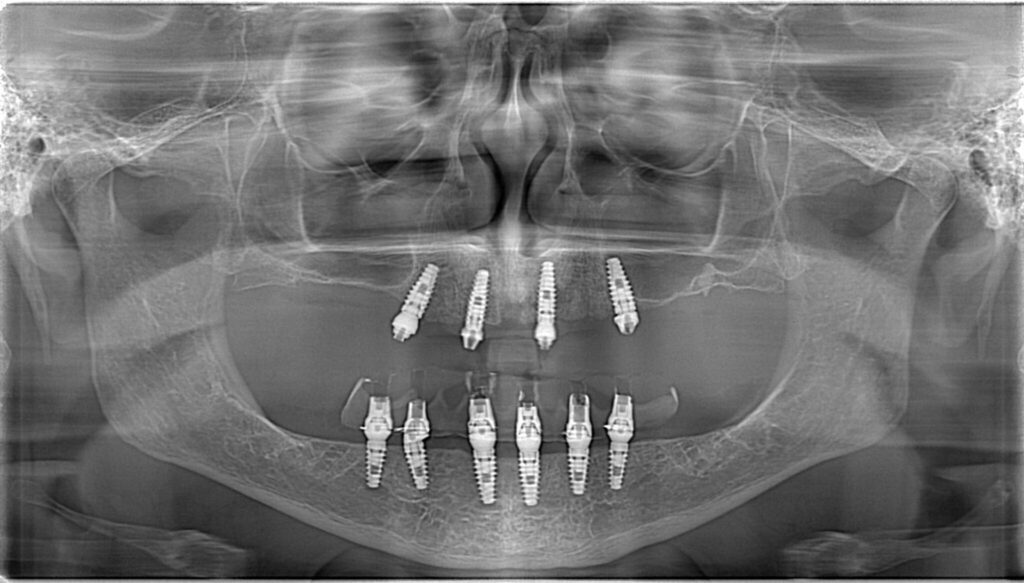

At Elite Dental of Summerfield, we provide implant dentures to restore your smile with enhanced stability, comfort, and functionality. Our team specializes in…